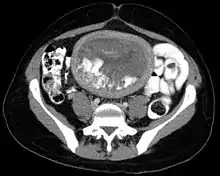

خانم باردار با علائمی مثل خونریزی و لکهبینی به دنبال تاخیر پریود مراجعه میکند. جواب آزمایش حاملگی HCG مثبت است ولی در سونوگرافی کیسه جنینی و قلب مشاهده نمیشود بلکه نمای پرزهای جفتی غیرطبیعی دیده میشود. بیمار تهوع و استفراغ شدید، رحم بزرگتر از سن حاملگی و گاه دفع بافتهایی از رحم به صورت خوشه انگور دارد.